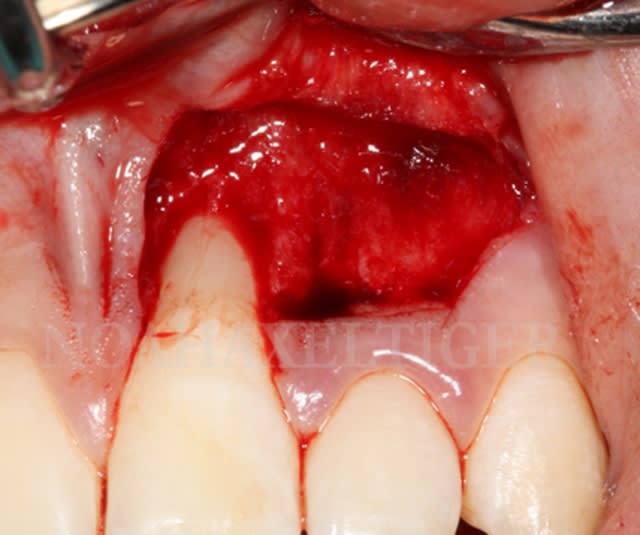

Dans le cas suivant, l'atteinte interproximale 31-41 n'autorise malheureusement aucune solution de recouvrement radiculaire :

Img 8511 llqbsh - Eugenol